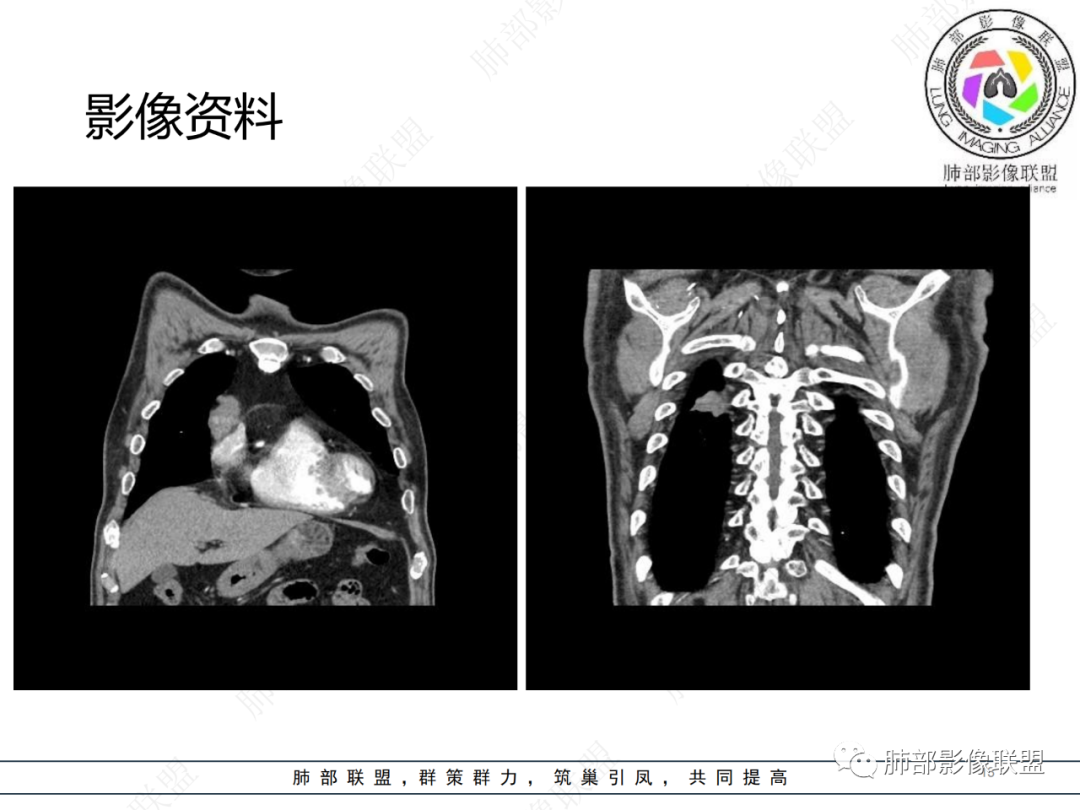

老年男性,体检发现纵隔占位,胸部CT检查所见,前纵隔多发软组织结节或肿块,右侧胸膜结节,密度均匀,边缘分叶,未见明显坏死,强化尚明显均匀强化,冠状位第1张图,左侧膈肌连续性中断,未见明确脾脏显示,可以考虑转移?异位组织(异位脾脏)?如果左侧膈肌确实断裂且无脾脏那么考虑异位脾脏可能大,或者代偿的淋巴结,再有鉴别神经源性肿瘤,入鞘瘤,不过鞘瘤一般会有ab区,这个病例没有。

前纵隔结节及右肺下叶背段胸膜下结节,增强扫描明显强化,所示图像未见脾脏,考虑异位脾并神经源性肿瘤或孤立性纤维瘤,鉴别胸腺瘤并神经源性肿瘤或孤立性纤维瘤。

右前纵膈不规则软组织密度影,密度均匀,分叶,中度强化,心包受侵,右侧胸膜不规则结节,明显强化,考虑胸腺瘤B2或B3型伴胸膜转移,鉴别胸腺癌

老年男性,前纵隔软组织结节灶,分叶状,偏于右侧,右侧胸膜亦可见结节灶,考虑高危型胸腺瘤或胸腺癌侵及胸膜